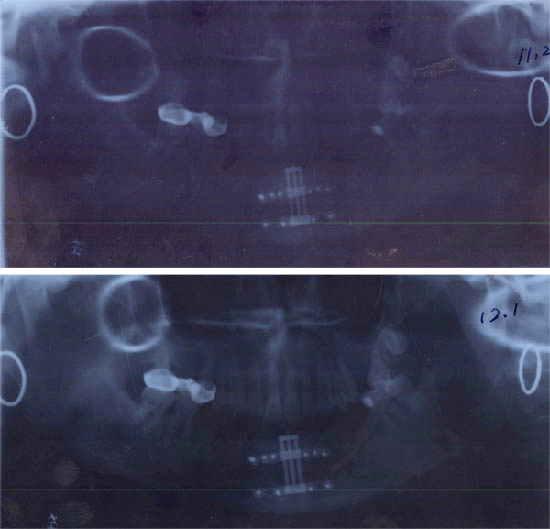

杨××,女,54岁,99年11月底因口底癌,在我院行右侧根治性颈扩清+口底癌扩大切除术+5+5的下颌骨的方块切除术+双侧颊膜瓣口底修复术。术后经过1年多的临床观察,病情稳定。患者要求义齿修复,因其下颌骨前部缺失,已低于唇,舌侧软组织,所以修复很困难,需增加牙槽嵴高度。2000年11月8日全麻下行垂直牵引器植入术。经过术后7天间歇期,于11月14日每天1次牵引升高移动骨段,于11月3日牵引结束,共升高12MM,已达到术前设计要求,经过8周的稳定期后,经X线片检查见骨间隙内新能生成良好,移动骨段稳定,牙槽明显恢复。经过半个月的软组织恢复。于3月末给预铸造活动义齿修复,其面型及咀嚼功能均得到了比较理想的恢复。